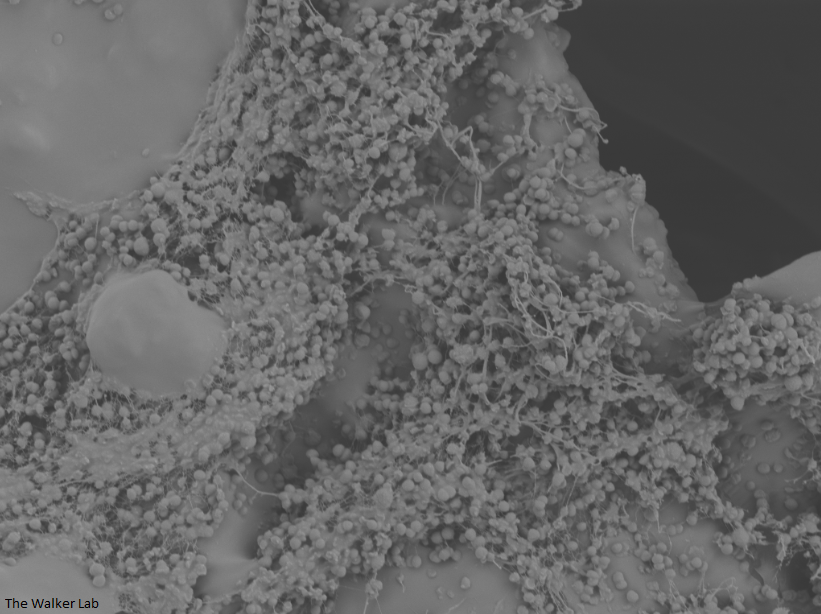

Host Immune Cells and Glycoproteins

Host Immune Cells and S. aureus

The host inflammation response to the catheter recruits immune cells and wound healing proteins which are deposited on the catheter surface. Atypical pathogens can use these host factors to adhere to the catheter's large surface and create biofilm. Colonization of catheters occurs quicker than expected and develops even in the presence of prophylactic antibiotic therapy. MRSA is just one of the uropathogens that can attach to the altered urinary catheter surface. One host factor deposited on the catheter surface is fibrinogen. We recently discovered that MRSA binds fibrinogen to attach to the catheter surface and form biofilm, which increases antibiotic recalcitrance. Our future studies aim to develop new non-antibiotic strategies that interfere with those interactions to prevent or treat CAUTIs.